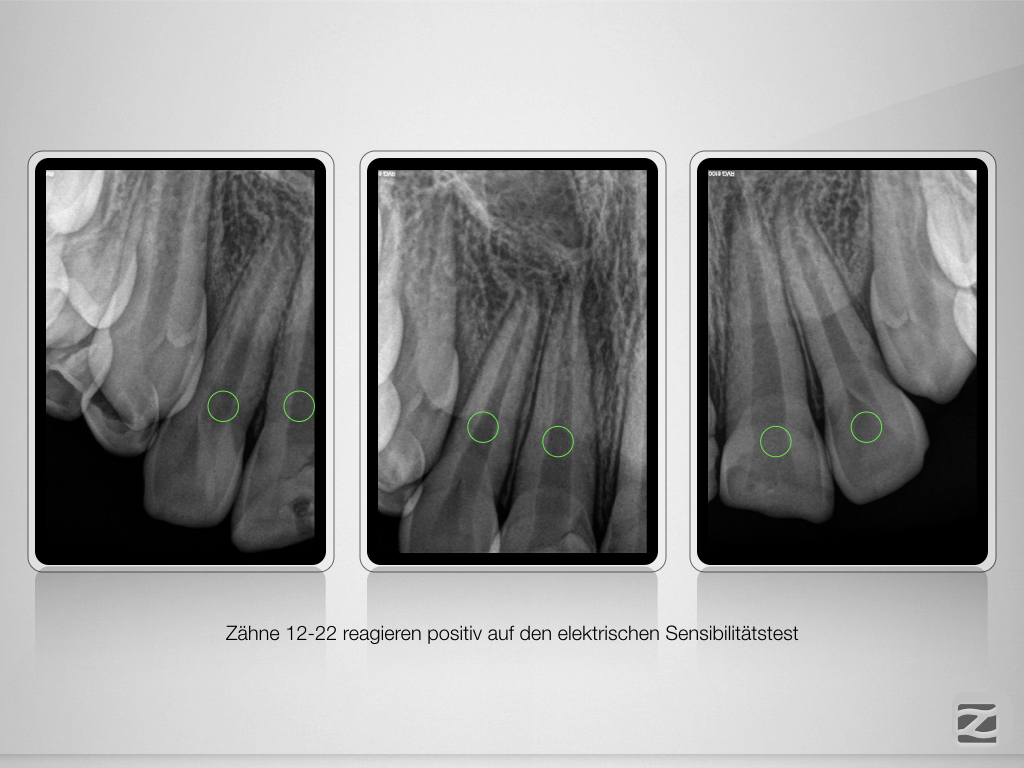

And the show goes on-Trauma, die Zweite.